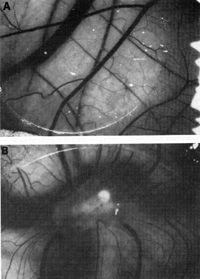

Fig. 9 A, B. Angiogenesis in chick chorioallantoic membrane. A Fixed (0.00125% glutaraldehyde) cells gave a negative result. B Metabolically active cells gave a strongly positive result. (From [42], with permission; Copyright 1988 by the American Association for the Advancement of Science)

Since there has been a great increase in the incidence of Kaposi's sarcoma in HIVinfected people, more so in male homo sexuals, one can speculate that HIV infection plays some role. It is not known whether any new or unknown viruses playa role in AIDS-related Kaposi's sarcoma. We started to explore the possibility of other virus(es) but did not find any. In the process, we developed a system for studying Kaposi's sarcoma [41,42].

The important thing that came out of our studies over the last few years is that we have a system in the laboratory for studying Kaposi's sarcoma. We can grow the spindle cells which are believed to be the tumor cells of Kaposi's sarcoma. Figure 8 shows the spindle cells derived from a person with Kaposi's sarcoma which were grown for several months in culture. We have several such cell cultures now. These spindle cells have been analyzed in collaboration with Judah Folkman and his associates from Harvard university [43]. They have the properties of primitive smooth muscle cells of vascular origin, as well as some properties of endothelial cells. We think then that the precursor cell of Kaposi's sarcoma is a mesenchymal, primitive precursor of cells of the blood vessel walls. Although we could not find any virus, particularly HIV-1, in these cells, it was found that they release a number of cytokines that have powerful angiogenic activity, which is a key feature of Kaposi's sarcoma. Figure 9 shows angiogenic activity released by the spindle cells grown in the culture tested in the normal chick chorioallantoic membrane [41]. One can take either the intact spindle cells or the concentrate of factors released from them and apply it to the membrane. Distinct angiogenic activity is observed in both instances. More interestingly, these spindle cells, when put into a nude mouse, cause a tumor similar to human Kaposi's sarcoma to develop (Fig.10). The lesion develops near the site of inoculation of the spindle cells within 10 days. When the spindle cells regress, the lesion dies out. We examined the lesion histologically. It appears like early Kaposi's sarcoma with blood vessel proliferation, fibroblasts,